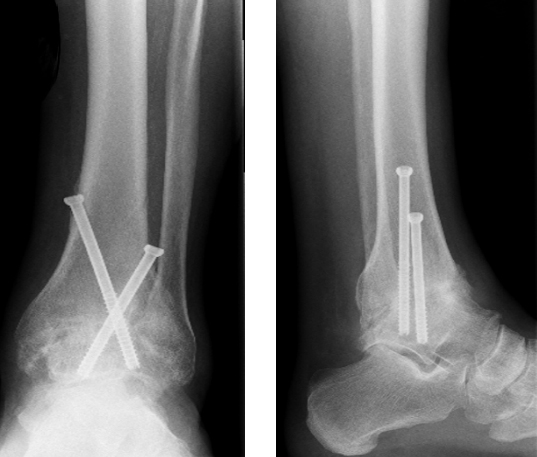

Bei voroperierten Patienten oder Patienten mit größeren Knochendefekten wie bei einer Hämophilie A (Bluter-Krankheit) sind komplexere Techniken mittels Verplattungen oder retrogradem Einbringen eines Marknagels unter Mitnahme des unteren Sprunggelenkes notwendig. Teilweise muß der knöcherne Defekt dann mittels Knocheninterponat überbrückt werden.

Versteifung des oberen und unteren Sprunggelenkes mit Knocheninterponat bei hämophilem Patienten (linke 3 Bilder) - Revision mittels retrogradem Nagel